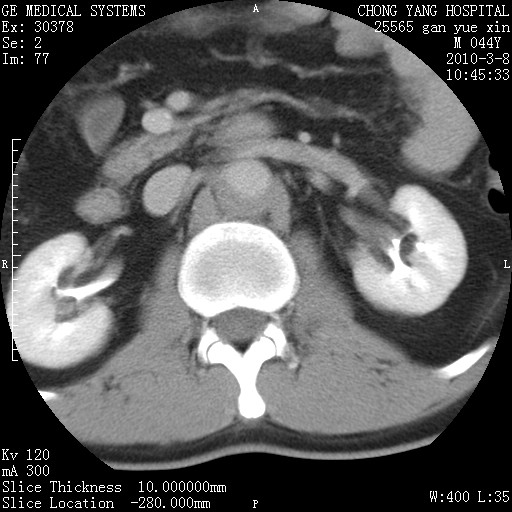

标题: CT24940:主动脉增强,典型病例。 [打印本页]

标题: CT24940:主动脉增强,典型病例。

夹层动脉瘤。

动脉夹层

夹层动脉瘤,典型

主动脉夹层。

动脉夹层的分型:

⒈debakey分型:根据主动脉夹层累及部位,分为三型:ⅰ型:原发破口位于升主动脉或主动脉弓部,夹层累及升主动脉、主动脉弓部、胸主动脉、腹主动脉大部或全部,少数可累及髂动脉。ⅱ型:原发破口位于升主动脉,夹层累及升主动脉,少数可累及部分主动脉弓。ⅲ型:原发破口位于左锁骨下动脉开口远端,根据夹层累及范围又分为ⅲa,ⅲb。ⅲa型:夹层累及胸主动脉。ⅲb型:夹层累及升主动脉、腹主动脉大部或全部。少数可累及髂动脉。

⒉stanford分型:a型:夹层累及升主动脉,无论远端范围如何。b型:夹层累及左锁骨下动脉开口以远的降主动脉。

夹层动脉瘤,少量胸水

夹层动脉瘤;左侧少量胸腔积液。

典型主动脉夹层。